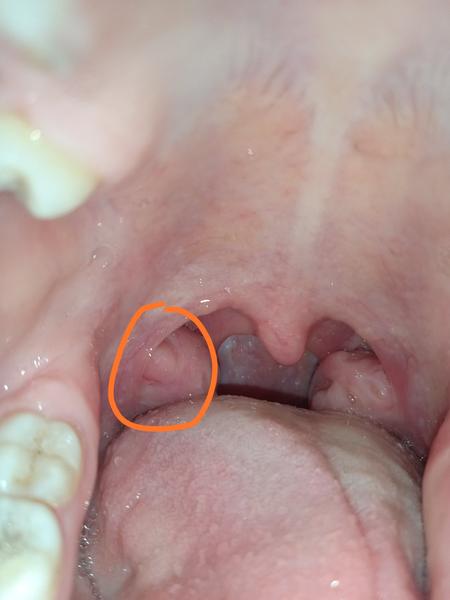

Aký je toto výrastok?

Na mandliach mi vysliel pred týždňom niejaky výrastok.